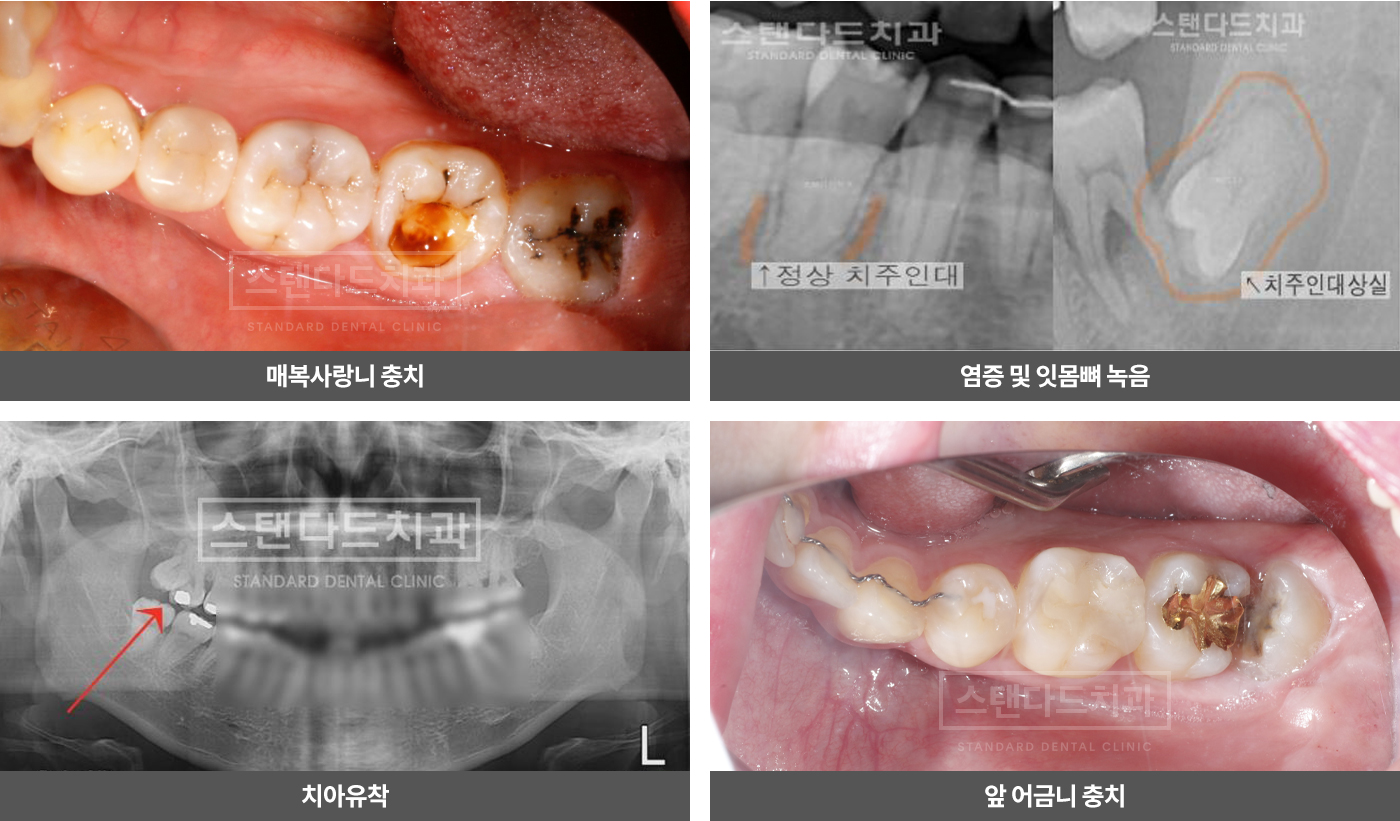

사랑니를 방치한다면